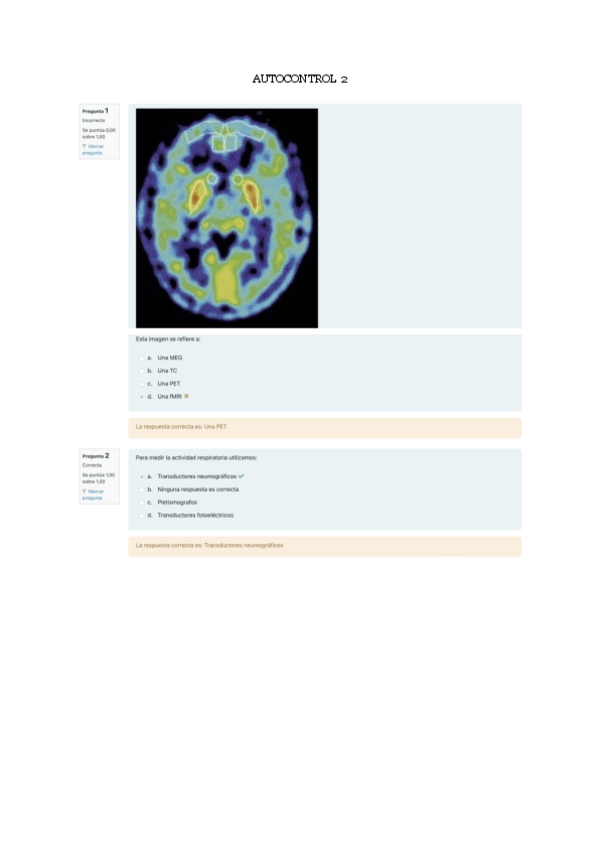

Autocontrol-2-Psicofisiologia.pdf